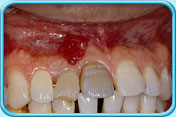

原因二

牙齒壞死

因碰撞或蛀牙導致牙齒壞死,壞死的牙髓所釋出的物質滲入象牙質,牙齒就會逐漸呈灰黑色。

治療方法

這類因牙髓壞死而引致的牙齒變色,必須以根管治療 (牙髓治療) 處理。

根管治療後若經根管治療後牙齒仍然呈灰黑色,牙科醫生可為牙齒進行牙齒漂白、貼面修復治療或人造牙冠鑲配。